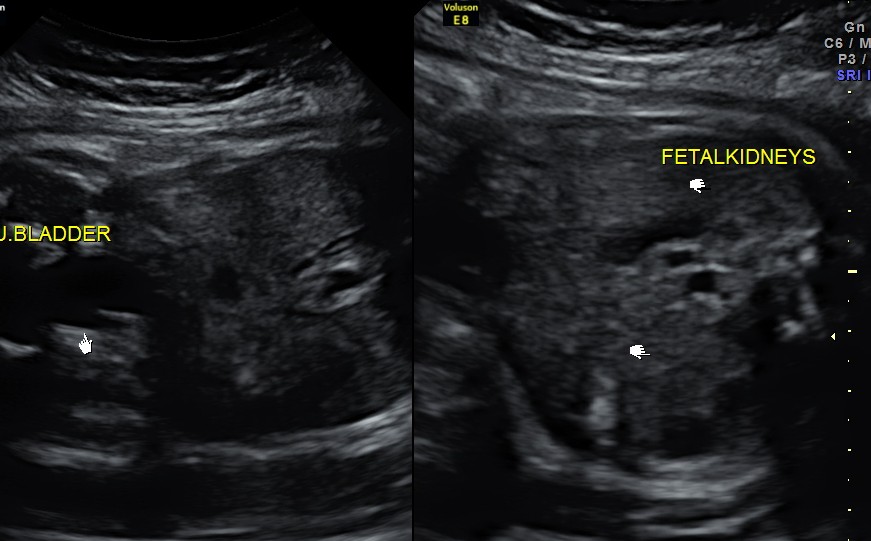

https://kriznanultrasoundimages.com/2013/05/12/tetralogy-of-fallot-tof/ at this time there was a revision of the cardiac findings : LEFT ATRIAL ISOMERISM WITH TETRALOGY OF FALLOT The irregular rhythm was not made out now. Apart from this the foetus has symmetrical IUGR and oligohydramnios Now the child was brought when she was 51 days old . She was born prematurely at 33 weeks of gestation . She had been seen at three higher institutions . The paediatric cardiologist has given a working diagnosis of CONO TRUNCAL VSD. But the catch was that the child had renal dysfunction with s .creatinine around 2 mgms and the ultrasound could not visualise the left kidney. The right kidney was reported to be hyperechoic . The following 2 pictures were of the fetal kidneys , as seen during the scan earlier.

The following two pictures show the hyperechoic kidneys of the child with mild pelvi calyceal dilatation . The kidneys were picked up only with the 11 mhz transducer.